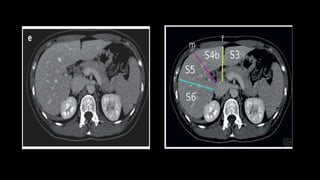

• There are eight liver segments.

• Segment IV is divided into segment IVa and IVb according to Bismuth.

• The numbering of the segments is in a clockwise manner.

• Segment I (the caudate lobe) is located posteriorly.

• The right portal vein divides into

anterior (supplying segments 5 and 8)

and posterior (supplying segments 6 and

7) branches.

• The left portal vein may be divided into

transverse and umbilical portions.

• The main branches of the left portal vein

originate from the umbilical portion, and

supply liver segments 2, 3 and 4